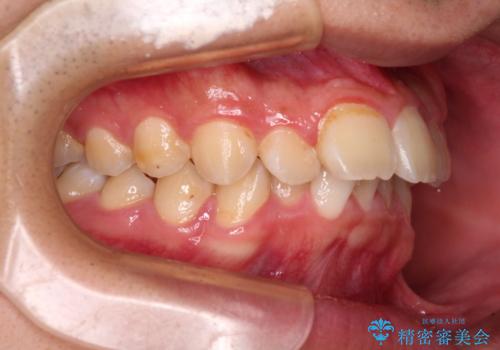

下顎の歯列は、奥歯が前方に傾斜し、前歯が上顎の歯の付け根に食い込むように内側に傾斜していました。

また、左右の犬歯の位置関係は上顎歯列が前方に位置する咬み合わせとなっており、インビザライン単体で治療するよりは、ワイヤー装置や補助装置を併用した方がより良い仕上がりになることが期待されました。

来院時は学生であったので、補助装置により上顎臼歯を後方に移動させ、下顎歯列はワイヤー装置による傾斜を改善させ、就職のタイミングでインビザラインにて仕上げていくこととしました。